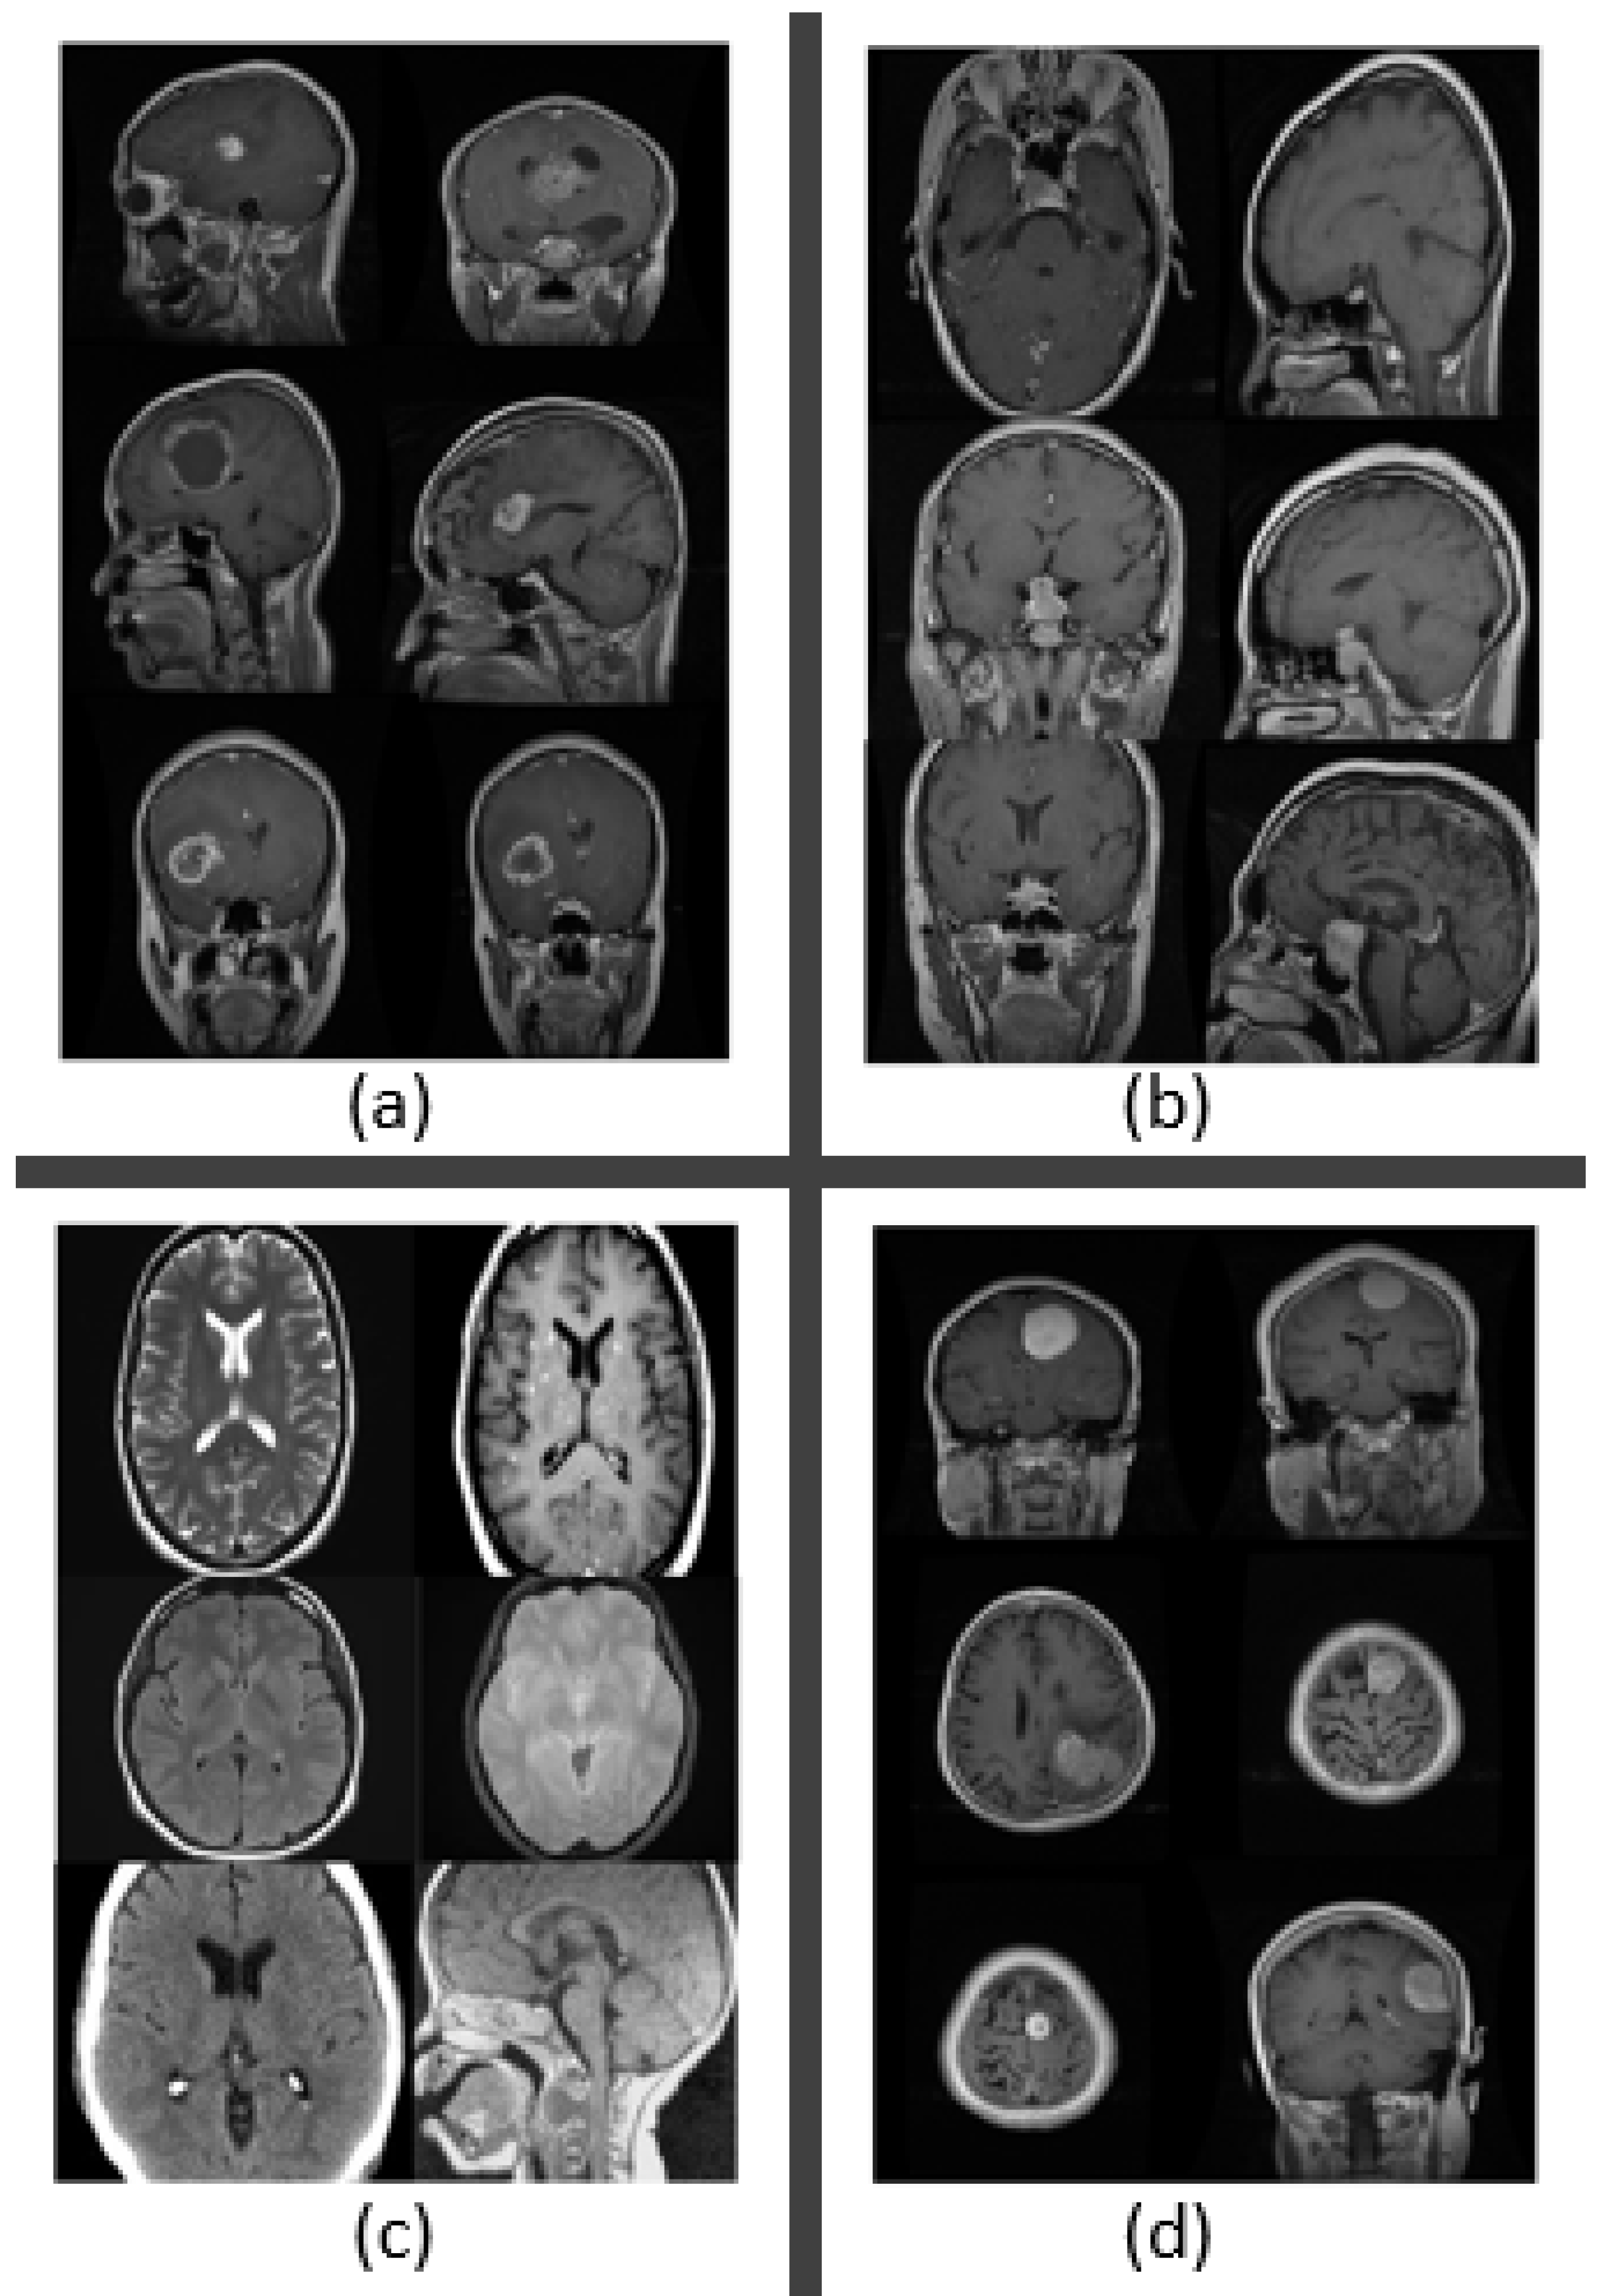

We obtained the dataset from publicly accessible online data on kaggle.com to detect brain tumors [45]. Images from magnetic resonance imaging (MRI) were used to construct the dataset. We selected MR images for our research since MRI is the best technique for detecting brain tumors. Meningioma (937 photos), no tumor (500 images), pituitary tumor (900 images), and glioma tumor (926 images) were the four different types of brain tumor data that we used in our study. In total, we used 3264 MRI data in our dataset. Table 2 displays the breakdown of the dataset, and Figure 4 shows the MR images according to the various forms of brain tumor.

Figure 4.

MR images of brain tumors. (a) Glioma tumor. (b) Pituitary tumor. (c) No tumor. (d) Meningioma tumor.